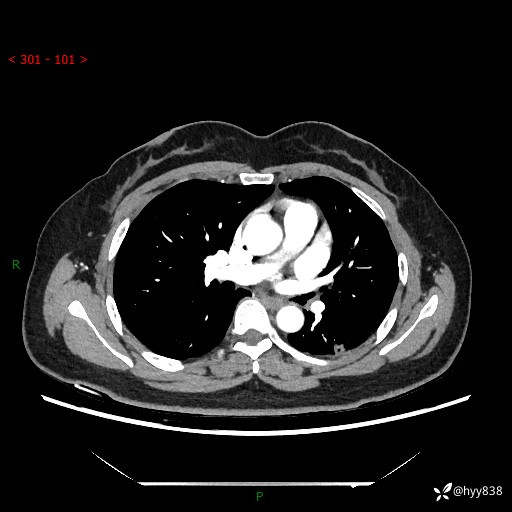

胸部CT平扫(2023.3)

胸部CT复查+增强(2024.6)